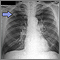

A solitary pulmonary nodule is a round or oval spot (lesion) in the lung that is seen with a chest x-ray or CT scan.

A solitary pulmonary nodule is most often found on a chest x-ray or chest CT scan. These imaging tests are often done for other symptoms or reasons. It can also occur as part of the screening chest CT for people age 50 to 80 years who have a 20 pack-year smoking history.